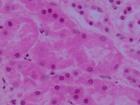

(4)腎組織檢查50%以上腎小球內有新月體形成;